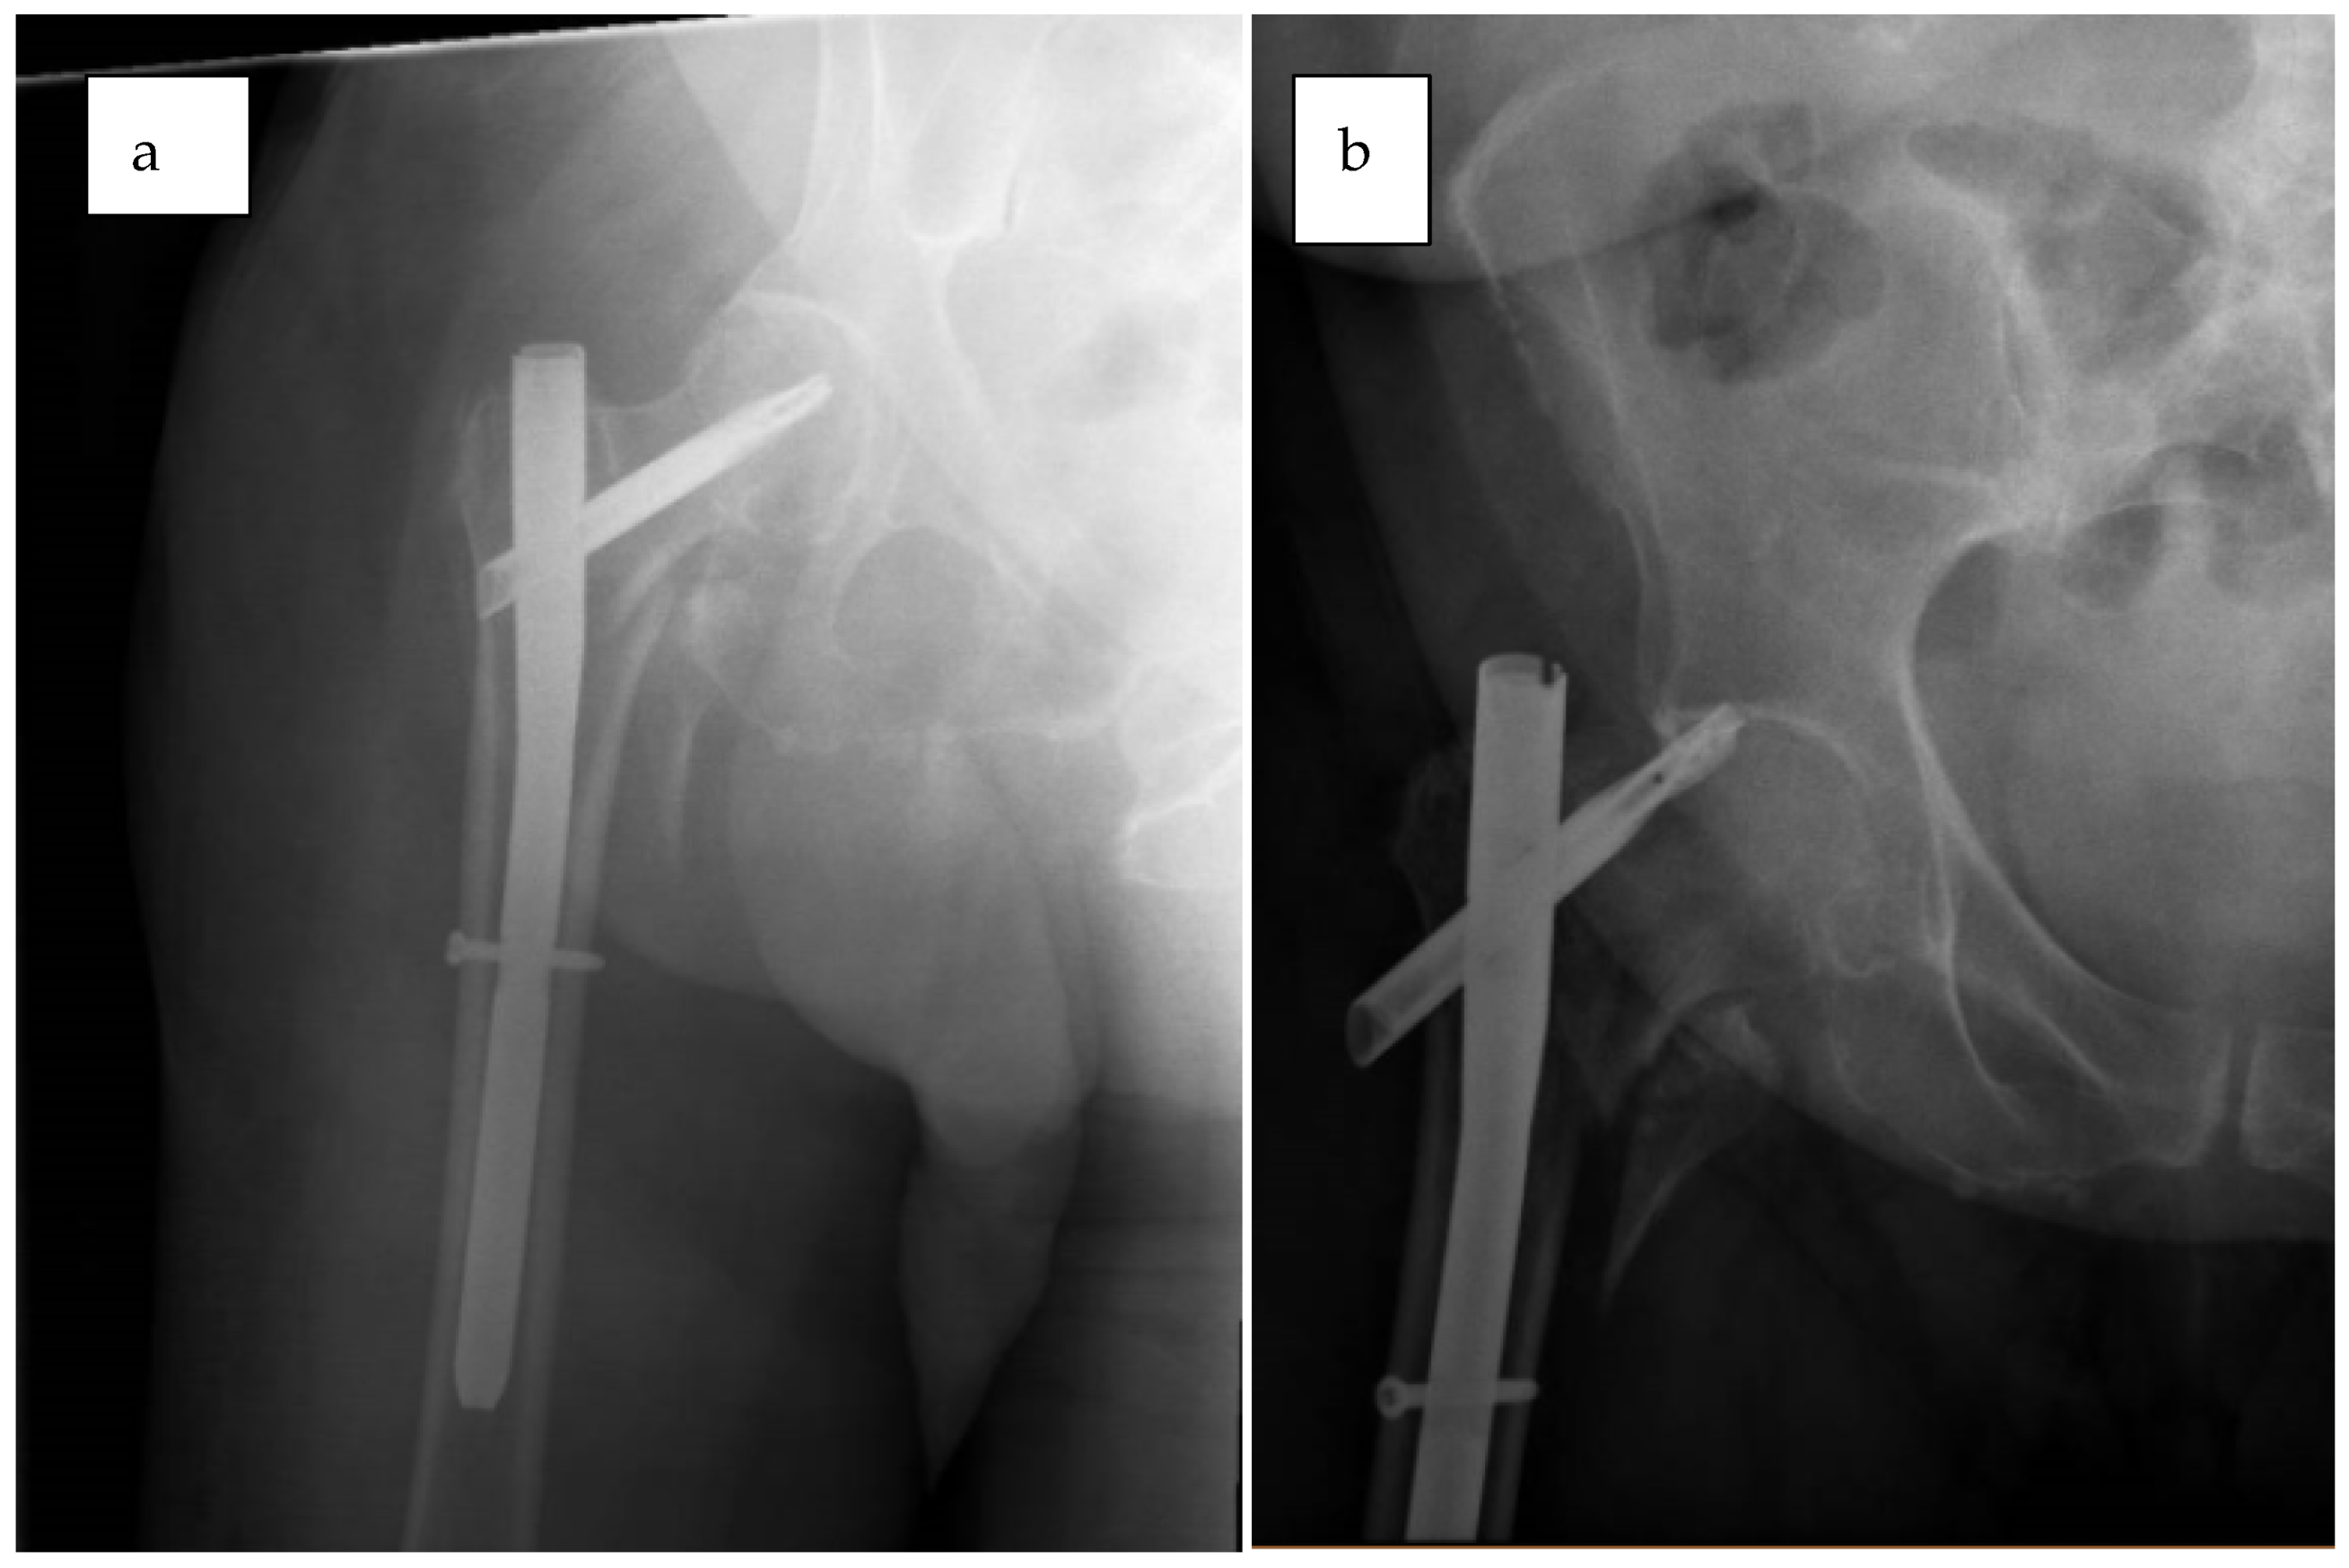

2.7.1. Case 1—Failure to Reduce Anatomically